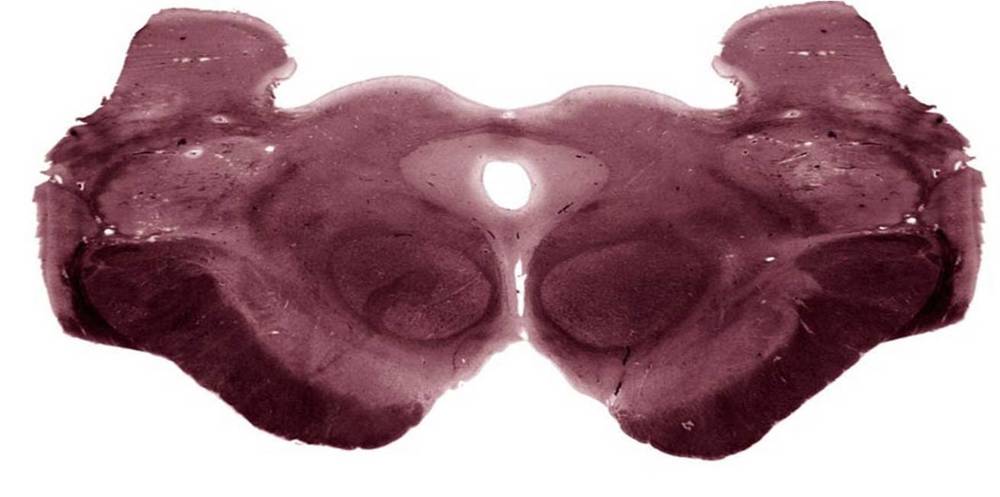

presiona la estructura marcada y escoge la opción que entregue la información correcta de la estructura.

Image:

d5870abf-d41c-4641-8643-eaeb7f2c1a73 (image/jpeg)

Answer

tacto fino de la mano contralateral.

tacto fino de la mano ipsilateral.

tacto fino del pie ipsilateral.

tacto fino del pie contralateral.